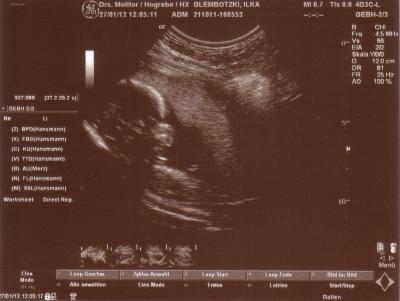

Nun haben wir die Bilder von Freitag mal eingscannt ;-) Das ist also bei 19+2 1. Bild = Profil 2. Bild = Popo zum Schallkopf, Beine in der Luft gespreizt und Prachtstück mittig platziert *lach* (das eindeutige Outing)